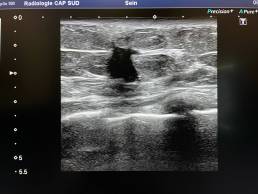

L’échographie retrouve une lésion à contours irréguliers, hypoéchogènes du sein gauche.